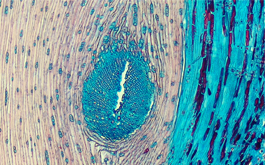

Color Tissue Section TrueChrome Metrics